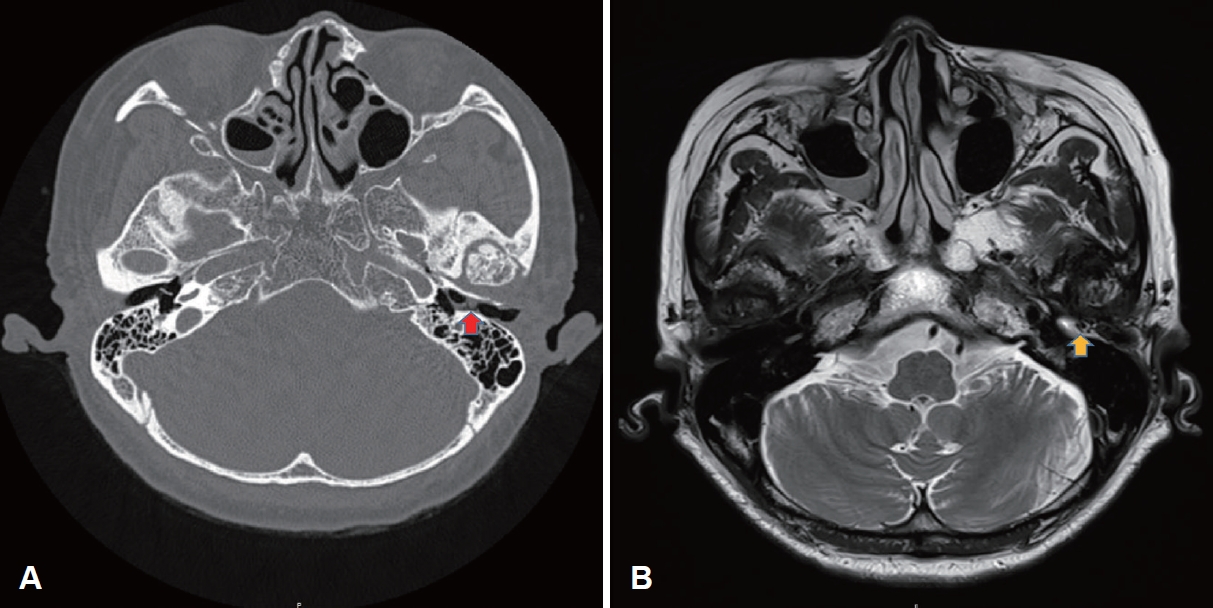

For the initial treatment of the subject, 3rd-generation cephalosporin antibiotics and low-dose steroids were used for 2 weeks, with suspicion of an inflammatory polyp. Cholesteatoma could not be ruled out as temporal bone CT showed an 8 mm iso-dense mass and diffusion restriction in the diffusion- weighted image (DWI) of the temporal bone MRI (Fig. 3). However, as the mass grew over the weeks, an excisional microscopic biopsy was planned via a post-auricular approach. Although performing a biopsy in the outpatient clinic was considered prior to surgery, it was presumed challenging to obtain an adequate tissue sample due to the soft and pliable texture of the mass and its proximity to the tympanic membrane (TM). Moreover, given that definitive symptom relief would require complete excision regardless of the tumor type, and also considering the patient’s personal difficulty in making frequent outpatient appointments, prompt surgical intervention was chosen to minimize the number of hospital visits. During surgery, a poorly marginated mass with a broad pedicle in the EAC anterior and superior walls, partially invading the outer layer of the TM, was observed. Tympanomeatal flap elevation was performed, and the outer and middle layers of the TMs were separated with a round knife. The mass was resected en-bloc with the EAC skin and part of the outer layer of the TM using microscissors. The autologous temporalis fascia was inserted over the middle layer of the TM, covering bare bone in an overlay method for reconstruction. The histopathological finding of the resected mass was consistent with myxoma, as the lesion was composed of spindle-shaped cells lying in a loose-textured, well-vascularized myxoid stroma (Fig. 4).

Unlike a simple inflammatory polyp, which is an acute condition, EAC cholesteatoma is a chronic inflammatory condition characterized by the proliferation of keratinizing squamous epithelium within the epithelial-lined canal of the EAC, leading to bony destruction. EAC cholesteatoma is frequently found on one side in relatively middle-aged and elderly individuals with normal hearing [7]. Whereas temporal bone CT is the method of choice to localize EAC cholesteatoma by confirming bony erosion or destruction, conventional MRI findings may be nonspecific. However, late enhancement of the lesion after 30 to 45 minutes from contrast administration may indicate cholesteatoma. The application of DWI in MRI is highly helpful, as cholesteatoma depicts high signal intensity due to diffusion restriction [8]. It is challenging to distinguish myxoma from cholesteatoma, as both appear with high intensity on T2-WI and either low or homogeneous intensity on T1-WI. They are also generally either hypodense or isodense in temporal bone CT [9]. The most significant difference is that cholesteatoma usually involves substantial bony erosion in CT, whereas myxoma rarely does. The differences in imaging features between EAC cholesteatoma and myxoma are shown in Table 2.

NotesAuthor Contribution Conceptualization: Jung Mee Park. Data curation: Jun Seop Kim, Sukjune Byun, Chang Heum Han. Formal analysis: Jung Mee Park. Investigation: all authors. Project administration: Jung Mee Park. Resources: Jung Mee Park. Supervision: Jung Mee Park. Visualization: Jun Seop Kim. Writing—original draft: Jun Seop Kim, Jung Mee Park. Writing—review & editing: all authors. Fig. 1.Otoscopic images of the lesion. A: Pre-operative otoscopic image shows a reddish, round mass occluding the left external auditory canal (EAC). B: Post-operative otoscopic image at 6 months shows a clear neotympanic membrane and EAC. Fig. 2.Pure-tone audiometry of the patient. A: Pre-operative pure tone audiometry shows a moderate to severe mixed hearing loss on the left side. B: Post-operative pure tone audiometry shows a reduced air-bone gap. Fig. 3.Radiological images of the lesion. A: Temporal bone CT. Soft tissue lesion in the left external auditory canal (EAC) with tympanic membrane (TM) thickening (red arrow) but without any bone lysis. B: Temporal bone MRI. 8 mm non-enhancing T2-weighted image hyperintense mass at left medial EAC, abutting to TM (yellow arrow). Fig. 4.Pathological images of the lesion. A: Pathologic evaluation reveals a well-circumscribed mass with predominantly myxoid stroma and partly fibrocystic change (hematoxylin and eosin [H&E], ×10). B: Bland stellate- or spindle-shaped cells are scattered in the hypovascular myxoid matrix (H&E, ×100). C: Some muciphages are intermingled with thin strands of vessels (H&E, ×400). Table 1.Differentiating diagnostic features of various EAC tumors Table 2.Image features among EAC cholesteatoma and myxoma REFERENCES1. Andrews T, Kountakis SE, Maillard AA. Myxomas of the head and neck. Am J Otolaryngol 2000;21(3):184-9.